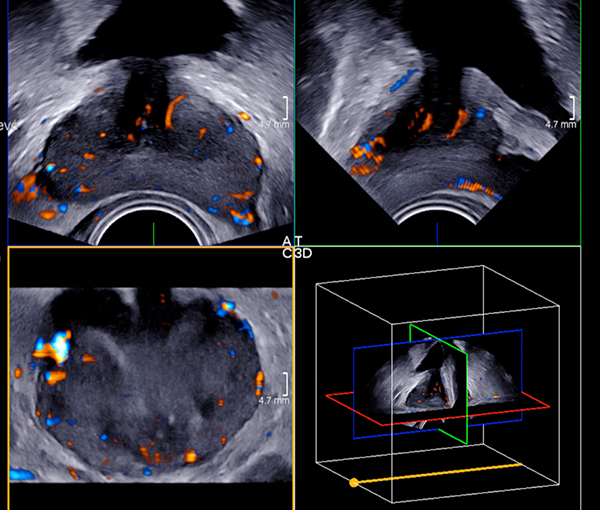

La biopsie prostatique, ou biopsie sous repérage échographique de la prostate, est une technique d’imagerie médicale visant à prélever de petits fragments du tissu prostatique afin d’en faire une analyse histologique, à la recherche d’un cancer de la prostate.

Chaque zone prélevée étant repérée en temps réel par le médecin radiologue, cette technique est d’une grande fiabilité.